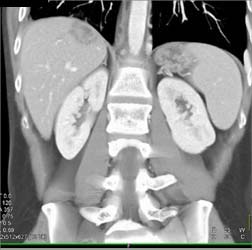

Neuroendocrine Tumor Invades the Portal Vein